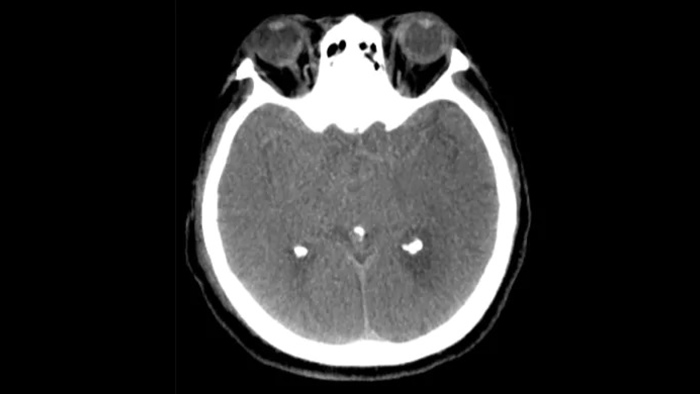

Revisión de hemorragias periprocedimiento

SmartCT Soft Tissue

Utilice las imágenes obtenidas mediante SmartCT Soft Tissue (similares a TAC convencional) en el paquete Neurovascular para comprobar el éxito del tratamiento y las hemorragias.